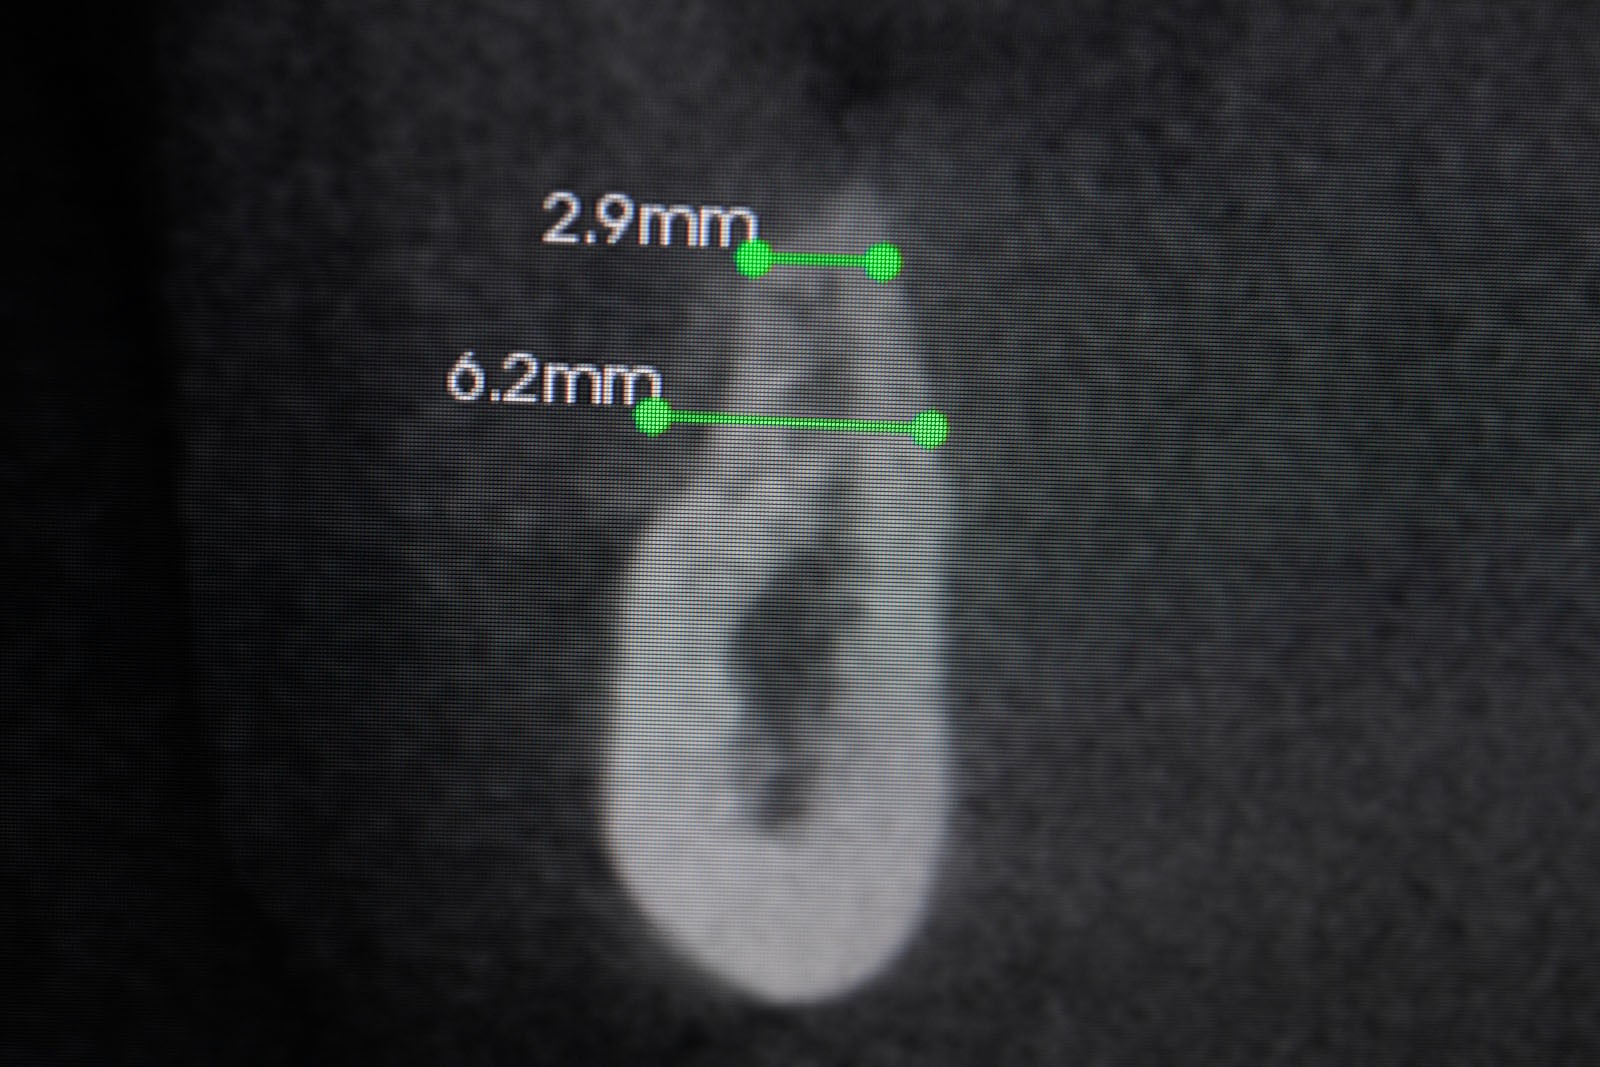

Przed podjęciem leczenia należy określić stopień zaniku kości szczęk oraz żuchwy. W tym celu przeprowadza się badanie kliniczne oraz odpowiednią diagnostykę obrazową pacjenta. Uwzględnia ona zdjęcie panoramiczne OPG jako podstawę dwuwymiarowego obrazowania podłoża kostnego oraz możliwe jest badanie tomograficzne CT lub bardziej precyzyjna tomografia stożkowa CBCT. Opcjonalnie wykorzystywana diagnostycznie tomografia pozwala na bardziej wnikliwą ocenę stopnia zaniku kości w trójwymiarowym, przestrzennym obrazie.

• Metoda otwarta – opisana w 1980 przez Jamesa i Boyna – polega na chirurgicznym dostępie do zatoki szczękowej poprzez jej boczną ścianę, następnie delikatnej preparacji, oddzieleniu wyściółki (błony Schneidera) bez jej perforacji, umieszczeniu pomiędzy nią a dnem zatoki materiału odbudowującego kość. Zabieg podniesienia dna zatoki szczękowej może przebiegać z jednoczesnym wszczepieniem implantów lub wszczepieniem ich w czasie odroczonym o 6–8 miesięcy. Warunkiem jednoczesnego wszczepienia implantów jest możliwość pierwotnie stabilnego ich umocowania w pozostałej własnej kości wyrostka zębodołowego. Najmniejsza jej ilość wg niektórych autorów to 1 mm.

• Metoda zamknięta – opisana w 1994 przez Summersa – bez szerokiego otwierania zatoki szczękowej, stosowana w sytuacjach wymagających niewielkiego zakresu rekonstrukcji na wysokość. W tej metodzie materiał regeneracyjny do odbudowy kości wprowadza się przez nawiercony kanał, komunikujący się z zatoką w pozycji zaplanowanej do wszczepienia implantu, lub tylko kondensuje się (zagęszcza, rozpycha i wydłuża) obszar kości dla uzyskania stosownej jej ilości i gęstości dla stabilnego umocowania implantu. Zabieg odbudowy kostnej wg Summersa wykonuje się przy użyciu specjalnego instrumentarium – zestawu osteotomów. Uzyskuje się dodatkowo 2–4 mm kości na wysokość

Precyzja projektu druku siatki bazuje na dokładności odwzorowania kształtu kości w stożkowej tomografii komputerowej CBCT, co zapewnia ich dobre przyleganie do podłoża kostnego oraz ogranicza powstawanie powikłań w postaci obnażania się siatek.